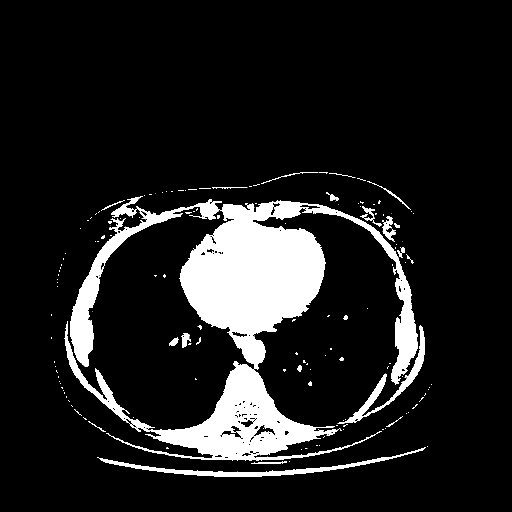

Reconstructed NATIVE CT scan (cycle consistency)

Full window (WL 1023.5, WW 4095 β†’ Low βˆ’1024, High +3071)

Actual HU range: [-1024.0, 3071.0]